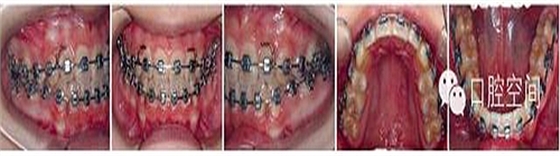

女性,11歲,表現(xiàn)為骨型Ⅱ類錯頜畸形,高角,下頜后縮,上下牙弓前突。X線片顯示正處于生長發(fā)育高峰期。治療前面頜像及X線片見圖2。通過拔除4個第一前磨牙,應用標準方絲弓定向力技術(shù)矯治,并在上頜第一磨牙近中植入種植體。初始弓絲上頜為0.017×0.022英寸不銹鋼方絲(1英寸=2.54 cm),下頜為0.018×0.025英寸不銹鋼方絲,佩戴高位J鉤牽引頭帽12小時/天,先牽引尖牙往遠中,再換用0.020×0.028英寸和0.019×0.025英寸不銹鋼方絲分別彎制關閉曲內(nèi)收上下切牙關閉間隙,在內(nèi)收前牙的同時,對上頜后牙進行垂直向的主動壓低。間隙關閉后應用10-2支抗預備系統(tǒng)直立下頜后牙,上頜始終通過高位J鉤牽引頭帽進行垂直向控制。最后下頜換用0.0215×0.028英寸全尺寸弓絲穩(wěn)定下牙列,使用Ⅱ類牽引和垂直牽引,對Ⅱ類關系進行過矯正。治療中面頜像見圖3。通過25個月的矯治,拆除矯治器,制作佩戴保持器。治療后FMA減少了1°,F(xiàn)MIA和Z角均接近正常值(表3),下頜骨垂直向生長明顯,治療后面型明顯改善,咬合關系良好。治療后面頜像及X線片見圖4,治療前后頭影測量對比圖見圖5。

圖3典型病例治療中面像